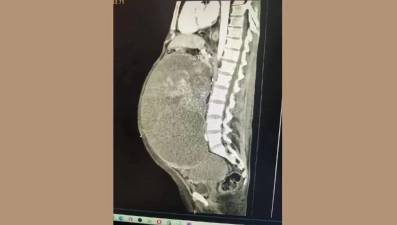

Опухоль яичника весом 10 килограммов удалили врачи областной больницы у 39-летней женщины. Новообразование занимало почти всю брюшную полость, сдавливало внутренние органы и представляло серьёзную угрозу жизни пациентки.